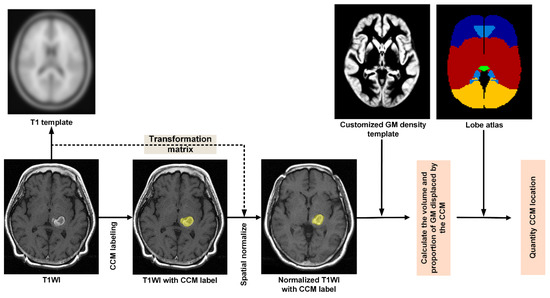

2.3. Quantitative CCM Evaluation

2.3.1. Stage 1–Preprocessing Control MPRAGE Images

2.3.2. Stage 2—Preprocessing of T1WI Images from Patients

- Step P5. Quantifying the displacement of GM by CCM

- Step P6. Quantifying lobe proportions within the CCM